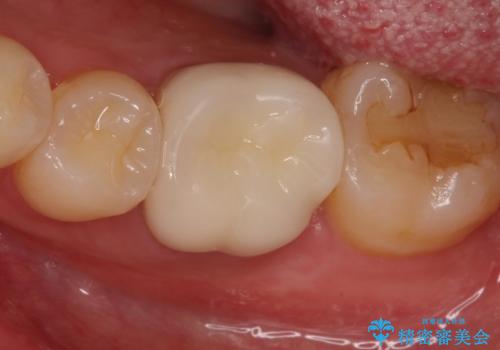

銀歯を除去し、セラミッククラウンに替えました。

審美性が良くなるだけでなく、拡大鏡を使用した治療、精度の高い材料の使用によって、虫歯の再発リスクを減らすことができます。